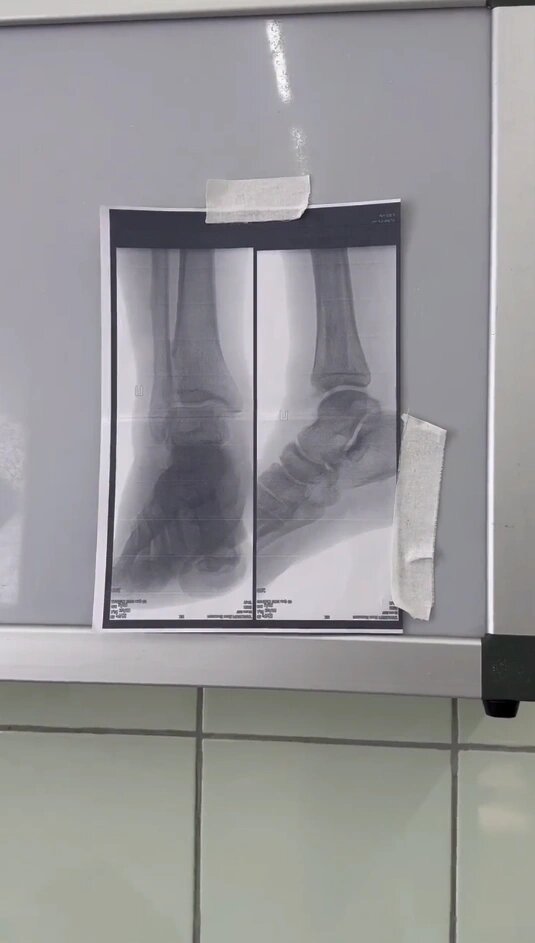

В больнице скорой медицинской помощи Новочеркасска рассказали о клиническом случае, связанном с гололёдом. Пациент, поскользнувшийся на улице, обратился за помощью лишь спустя двое суток после падения. В результате обследования у него был диагностирован изолированный перелом наружной лодыжки со смещением. Травматологи-ортопеды Рамин Ибрагимов и Николай Любимов успешно провели операцию остеосинтеза, установив титановую пластину и винты. Послеоперационный период прошёл без осложнений. На данный момент пациент уже выписан из стационара и будет продолжать лечение амбулаторно в поликлинике.

Фото: ГБУ РО "ГБСМП" в г.Новочеркасске